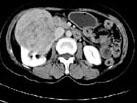

女,57岁,右腰部胀痛6月余,触及右侧腹部包块2月,CT平扫及增强如图所示,下列说法正确的是?(?)

• A.平扫时可见右侧腹部巨大的软组织肿块影,其内可见小片状的低密度影

• B.增强扫描肿块强化明显,其内可见无强化的低密度坏死灶

• C.考虑肿块来源于肝脏,是原发性肝癌,并挤压推移右肾

• D.考虑肿块来源于右肾,是巨大的肾癌,并挤压推移右肝,与其分界欠清

• E.考虑肿块来源于右肾,是肾血管平滑肌脂肪瘤,并挤压推移右肝,与其分界欠清